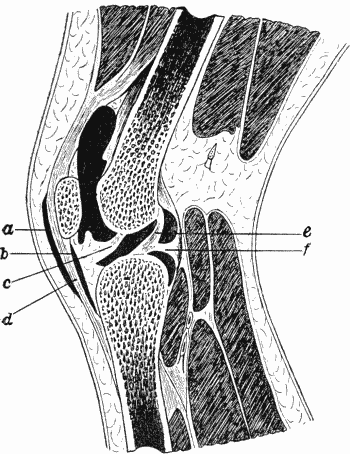

| 80. | Section of Knee-joint showing Extent of Synovial Cavity | 156 |